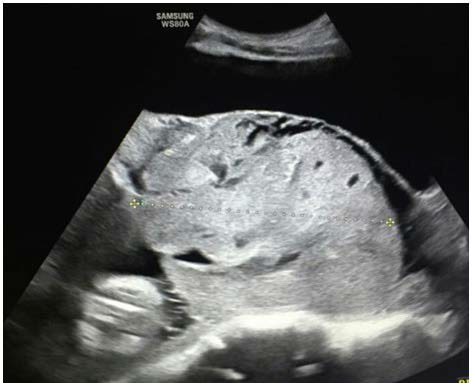

Figure 2: A greater magnification of the previous photo: the serosa layer divided the urinary bladder (on the top) from the placenta.

figure 2